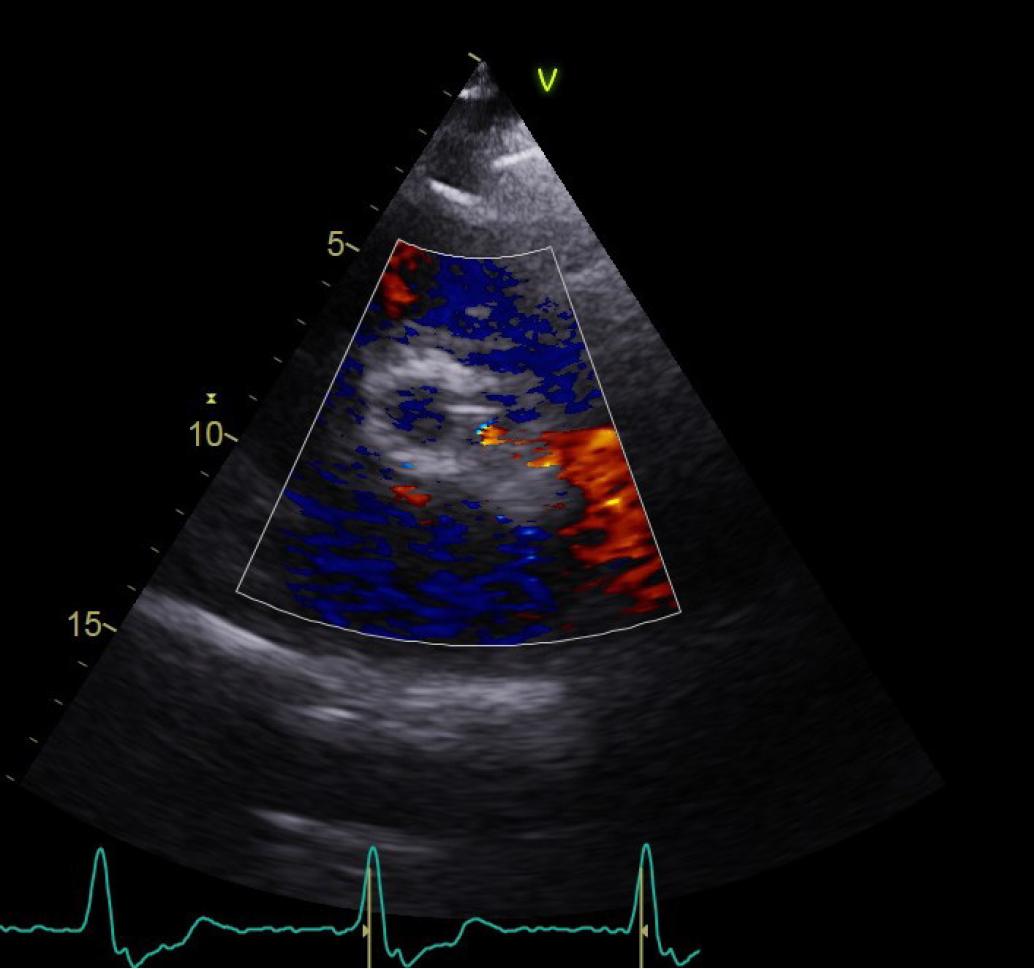

The TTE, performed after the procedure, revealed a mean transprothetic gradient of 13 mmHG, a minor paraprothetic leak with an approximate circumferential extent of 10% (Figure 3).

Transthoracic echocardiogram, parasternal short axis view of the paravalvular leak.